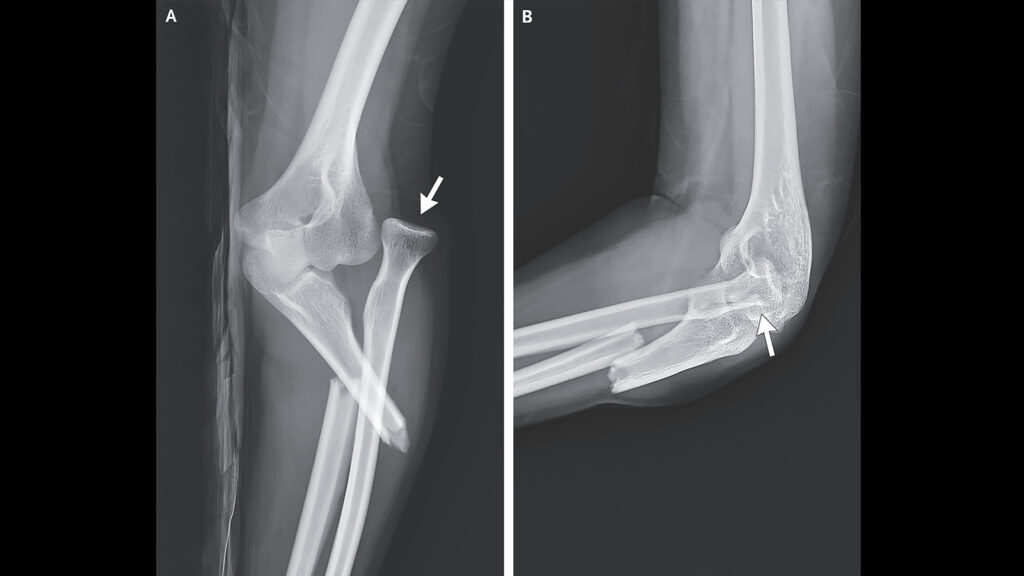

The 26-year-old arrived at the emergency department at Far Eastern Memorial Hospital in Taipei City, Taiwan, with…